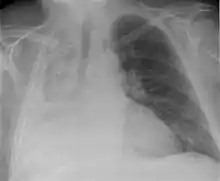

Atelectasis of the right lower lobe seen on chest X-ray.

Clinically significant atelectasis is generally visible on chest X-ray; findings can include lung opacification and/or loss of lung volume. Post-surgical atelectasis will be bibasal in pattern. Chest CT or bronchoscopy may be necessary if the cause of atelectasis is not clinically apparent. Direct signs of atelectasis include displacement of interlobar fissures and mobile structures within the thorax, overinflation of the unaffected ipsilateral lobe or contralateral lung, and opacification of the collapsed lobe. In addition to clinically significant findings on chest X-rays, patients may present with indirect signs and symptoms such as elevation of the diaphragm, shifting of the trachea, heart and mediastinum; displacement of the hilus and shifting granulomas.[10]